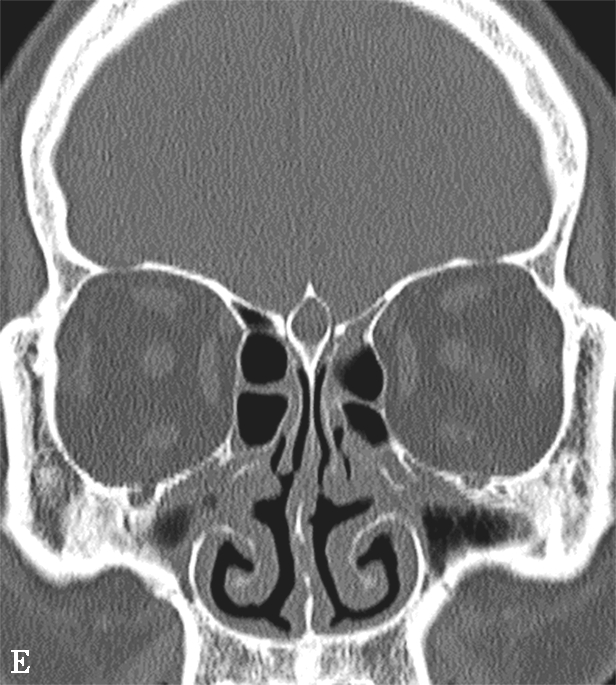

即中组筛房,位于鼻丘后,由1~3个气房构成,内下壁与筛骨钩突间形成半月裂间隙。筛泡过度气化,可能造成筛漏斗及半月裂狭窄,影响引流;过度气化至眶下壁时,称为眶下气房,又称Haller气房,也可能影响上颌窦的引流(图1-3-6)。

图1-3-6 筛泡解剖变异

A.双侧Haller气房;B.左侧筛大泡